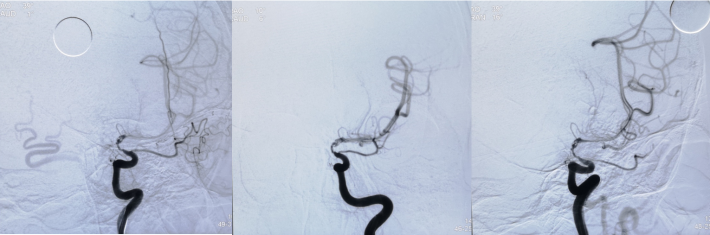

考虑狭窄段为夹层样改变,多角度导引导管造影,以更清晰地区分真假腔,选择最佳工作角度

微导丝通过狭窄血管段

放置微导丝远端至左侧大脑中动脉上干M2段

3mm*15mm球囊扩张

球囊扩张后